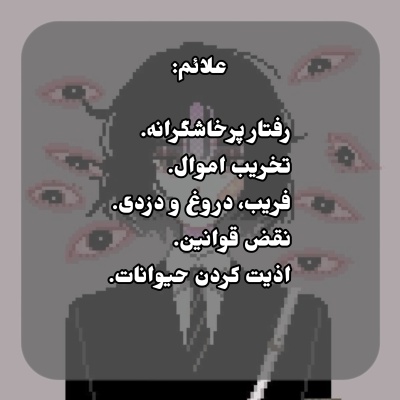

معرفی اختلال سلوک؛ اختلالی در رابطه با رفتار پرخاشگرانه کودکان و نوجوانان.